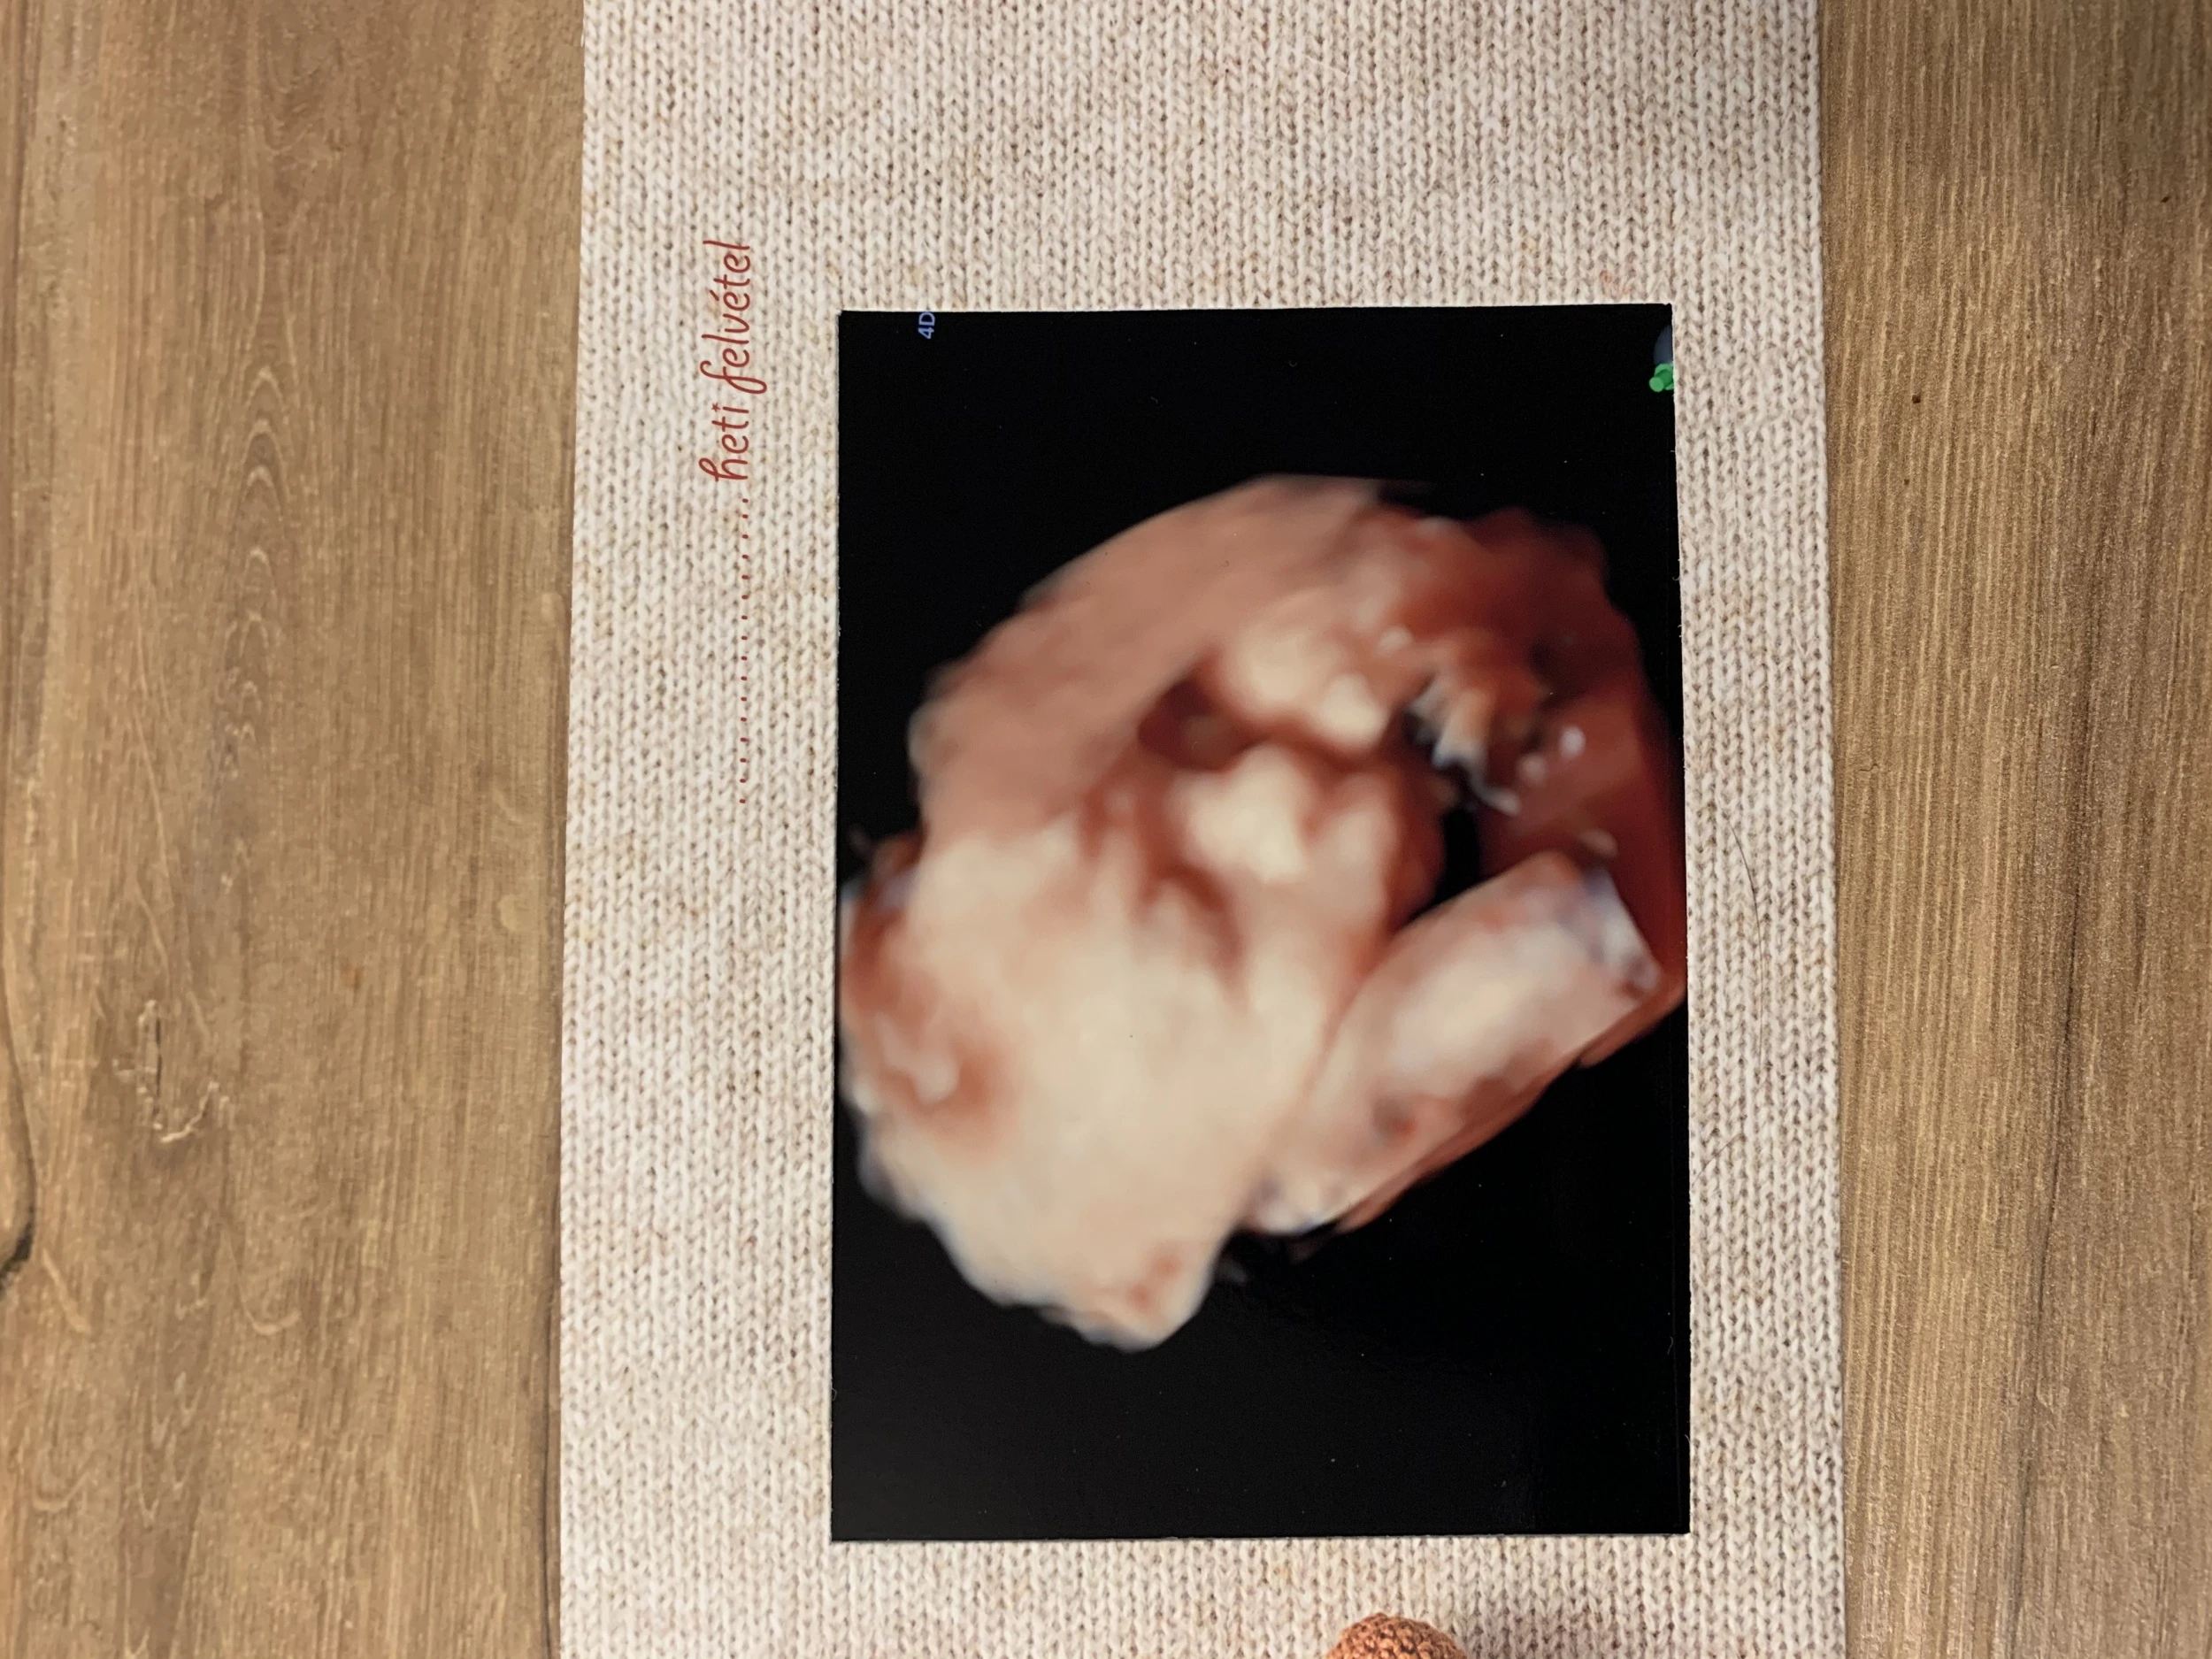

Ideje is volt hazajönnöm, hogy a család és az itthoni barátaim is láthassák élőben ezt a változást. Az ünnepek vészesen közelegnek, ami azt jelenti, hogy nekem még rengeteg intéznivalóm lesz Magyarországon. A szokásos őrült ajándék beszerző körutat igyekeztem a covidra való tekintettel internetes vásárlással megoldani, de az aktuális vizsgálataimon kötelező volt megjelennem. A terheléses cukorvizsgálat már azóta félelmet keltett bennem amióta tisztázódott számomra, hogy ezt el kell végezni a terhességem során. A tűtől való félelmem gyerekkoromból gyökeredzik, amit nem hogy legyőzni, hanem inkább elmélyíteni sikerült az idő múlásával. Sajnos gyakran el is szoktam ájulni utána, ami szintén nem könnyíti meg a helyzetem. Nagyon örültem volna, ha a férjem el tud kísérni, de ez kivitelezhetetlen volt. Bár Magyarországon tartózkodott éppen, hiszen az olasz klub csapata egy magyar együttessel játszott, de ilyenkor a többiekkel kell mozognia és szigorú napirendnek kell eleget tennie. Csak nagyon indokolt esetben kaphatna lehetőséget a távozásra, például szülés esetén, így tudtam, hogy ezt most egyedül kell megoldanom. Nem mondom, hogy nem gyönyörű a Citadella és környéke, de mikor a Bérc utca lankáin besétáltam korán reggel éhgyomorral a magánegészségügyi központ ajtaján, nem tudtam feltétlenül csak erre gondolni. De aztán felülkerekedtem ezeken az érzéseken. Amikor a glükózt tartalmazó löttyöt kellett felhajtanom arra gondoltam, hogy egy elrontott limonádé, ez lelkiekben némiképp segített. Szerencsére miután ez megtörtént nem volt időm sokáig sajnálni magamat, ugyanis időpontom volt ultrahangra. Átsétáltam az emeletre, ahol rögtön szólítottak és már kezdődött is a vizsgálat. Talán az előbb említett események miatt egy kicsit szórakozottan néztem a képernyőt. A vizsgálatot végző szakember először elsorolta az asszisztensének a méreteket, adatokat majd egy gombnyomással váltott és megláttam először 4D-ben a bennem ‘lakó’ kisbaba arcát. Nem

tartom magamat túl érzelgős embernek, de rögtön könny szökött a szemembe. Elképesztő élmény volt, amíg élek nem felejtem el. Az örömömet pár perc után kicsit beárnyékolta, hogy Gergő nem élhette ezt át velem. Természetesen, amint kijöttem az ajtón az első az volt, hogy elküldtem neki egy fotót, illetve még egy pendrive-ot is kaptam a felvétellel, így kicsit megnyugodtam, hogy nem maradt le teljesen az élményről.